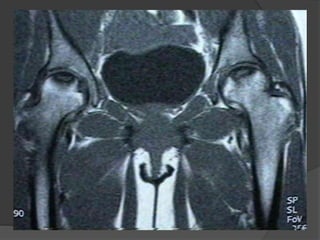

MRI

 An important feature in differentiating bone infarct from other

medullary lesions is that the central signal usually remains that of

normal marrow. The marrow is not replaced.

 T1

 serpiginous peripheral low signal due to granulation tissue and to

lesser extent sclerosis

 peripheral rim may enhance post gadolinium

 central signal usually that of marrow

 T2

 acute infarct may show ill-defined non-specific area of high

signal

 double-line sign: hyperintense inner ring of granulation tissue

and a hypointense outer ring of sclerosis

 absence of double-line sign does not exclude bone infarct